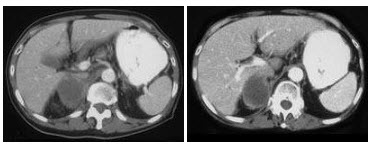

女,14岁,左腰部胀痛,CT平扫+增强如图所示,下列说法正确的是()

A.左肾实质内可见两个类圆形的囊性病灶,边缘光整,增强后不强化

B.左肾后外侧缘可见一较大的囊性病灶,其壁薄而光整,考虑为肾包膜下囊肿

C.左肾后外侧缘可见一较大的囊性病灶,其壁薄而光滑,考虑为肾外囊性病灶

D.考虑为多囊肾

E.考虑为多发性肾囊肿